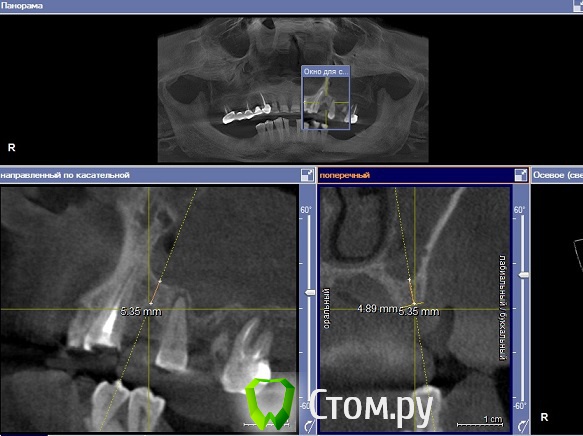

Yniversal Опубликовано 26 ноября, 2013 Поделиться Опубликовано 26 ноября, 2013 Здраствуйте уважаемые коллеги!Хотелось бы узнать ваше мнения по поводу тактики ведения данных пациентов , возможности проведения синус-лифтинга и имплантации.Спасибо 1. 15-продольная фрактура коронки и верхней трети корня.Изменения слизистой пазухи.Выведение ПМ за верхушку.Клиники синусита нет.16 перкуссия "-"2. После кт исследования проведены удаления 25 26 27. Клиника синусита не выражена.Пациент жалоб не предьявляет.3.16 удален несколько лет назад.Клиники со стороны пазухи не выявлено Ссылка на комментарий